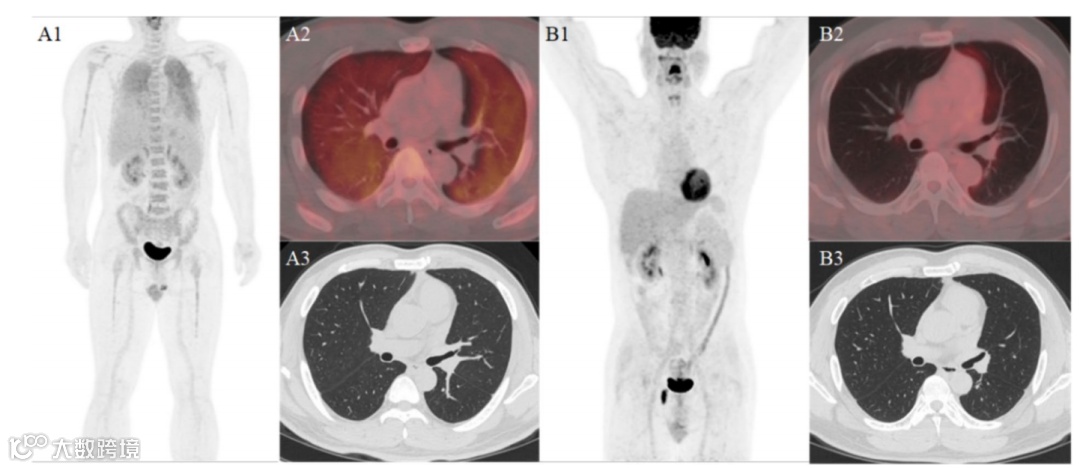

50岁男性,因“不明原因发热3月余”就诊,体温最高达39.3℃,抗感染治疗无效。常规检查无特异性发现,但胸部CT竟未见异常!然而,随后的全身¹⁸F-FDG PET/CT却显示:双肺弥漫性高代谢(SUVmax 5.1),伴骨髓摄取轻度增高(SUVmax 3.1)。

图1中,MIP图(A1)显示双肺及全身骨骼均出现弥漫性糖代谢增高;横断位PET/CT融合图(A2)显示双肺存在弥漫性糖代谢增高;横断面CT图像(A3)显示同台设备的高分辨率CT扫描未见明显异常;MIP图(B1)显示患者治疗后全身糖代谢未见明显异常;横断位PET/CT融合(B2)显示PET/CT融合影像未见明显异常;横断面CT图像(B3)显示同台设备的高分辨率CT扫描结果。

经4周期R-CEOP方案化疗后,复查PET/CT显示原高代谢灶完全消失,达到完全代谢缓解!